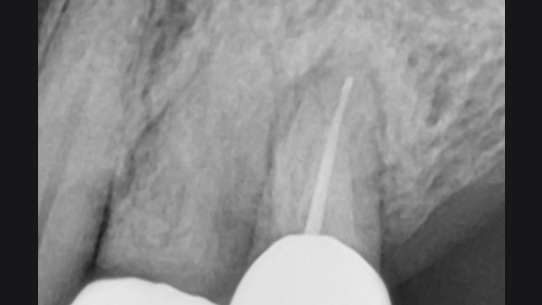

치아 뿌리 주변 염증과 치조골이 녹아내려 통증과 더불어 치아가 흔들리는 상태로 내원한 환자입니다. 우선 큐렛으로 잇몸 속 치석을 제거하였습니다. 뿌리 주변 염증은 신경관을 소독하고 약재를 삽입하는 신경치료를 시행하였습니다.

치근단 염증

신경관 소독

신경관 약재삽입

약재주입 후 반응